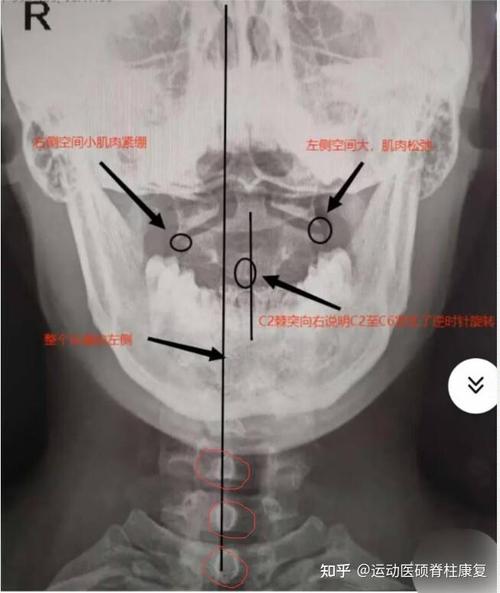

(图片来源网络,侵删)

给家长的建议: 如果您的孩子出现颈部疼痛、头部歪斜(斜颈)、活动受限(尤其是旋转困难)、拒绝转头等情况,无论近期有无感冒或外伤,都应及时就医,医生会通过详细的体格检查和影像学检查(如颈椎张口位X光片)来明确诊断,并排除潜在的严重疾病,对于大多数非外伤性的寰枢椎半脱位,通过休息、颈部制动(如佩戴颈托)、治疗原发感染(如感冒)等保守治疗通常可以取得很好的效果。